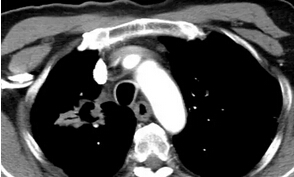

上圖:消融結(jié)束即刻掃描可見(jiàn)沒(méi)有氣胸等損傷。術(shù)后1月增強(qiáng)CT掃描,看到病灶完全沒(méi)有強(qiáng)化。第三位患者因肺癌接受過(guò)分子靶向治療,但一段時(shí)間以后病灶開始有反彈趨勢(shì),他聽病友介紹來(lái)門診咨詢并選擇了微波消融這種治療方法。

CT掃描看到右上肺一個(gè)2cm左右的病灶我們?cè)贑T引導(dǎo)下一次就把消融針穿入腫瘤中心,開始消融僅用了3分鐘就完成了消融手術(shù),患者幾乎沒(méi)有任何不適,結(jié)束了還一再懷疑時(shí)間是不是不夠。術(shù)后一個(gè)月增強(qiáng)CT復(fù)查,病灶完全壞死。患者的懷疑變成了折服。